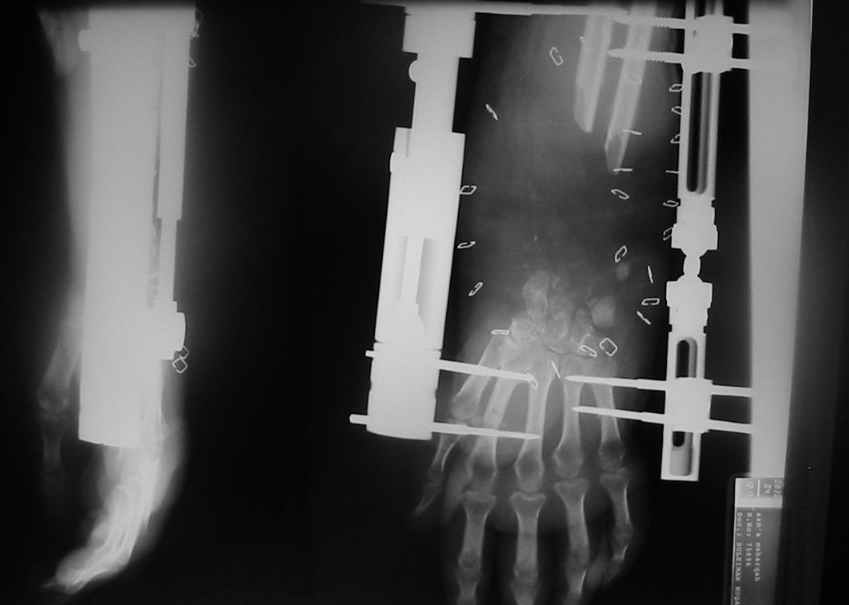

Uvazaemmie Kollegy!Zdastvuete!Bolnjia 33 goda, popala v DTP pochty 10 nedel nazad, beremennjia 30 nedel', poluchila sochetanio travmu grudnoi kletky i ODA: Perelom 4 reиber sleva, osloznenny pneutoraksom, otktrijia travma levogo predplechia: v rezultate chego, obrazavalsa deffect distalngo otdela obeix kostei predplechia okolo 10 cm., vmeste s sustavnoi poverhnosty luchevoi kosty, obsherny deffect miahkih tkany razgibatelnoi poverhnosty predplechia 15x20x15 cm. s polnim razmazeniem vseh razgibatelei na itom uravne, povrezdenjia mezkostnoi vetvy Rad. Nerve, i stvol medialnogo nerva, povrezdenjia loktevoi arterii. Pri postuplenii Proezvedena pervichnia obrabotka rany, fixasii s pomoshio dvuh mini apparatov Orthofix, bil' vostanovlen median nerve i loktevia arteria, cherez 5 dnei, deffect kozy bil zakrit', kist' spasena, beremennost' sohranena, 2 dnjia nazad', bolnia radila zdarovio devushku i nastal moment istiny: CHTO DELAT"?!

Аппаратное удлинение костей предплечья приблизительно на 4-5 см, после достижения стыковки с костями запястья фиксация мостовидной

пластиной (пластина кладется на лучевую кость и вторую пястную кость, вторая пластина на локтевую и фиксируется за четвертую пястную, между запястными костями и концом костей предплечья спонгиозная костная пластика) аппараты внешней фиксации додержать 3-4 недели как дополнительная

фиксация, затем убрать.

Acute shortening, extending of pins , exchange to Pediatric LRS ( of Orthofix), and osteotomy proximal for lengthening.Later you can achieve wrist arthrodesis with bone graft